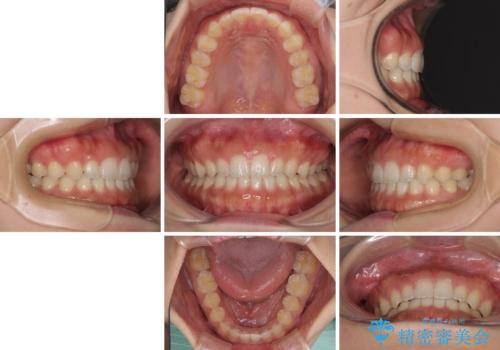

- 後戻りによる上下前歯の隙間を気にして来院された患者様です。

歯列不正はそれほど大きくなかったため、インビザライン・ライトを用いて矯正治療を行うこととしました。

無理のないペースで治療を進め、9ヶ月で終えることができました。